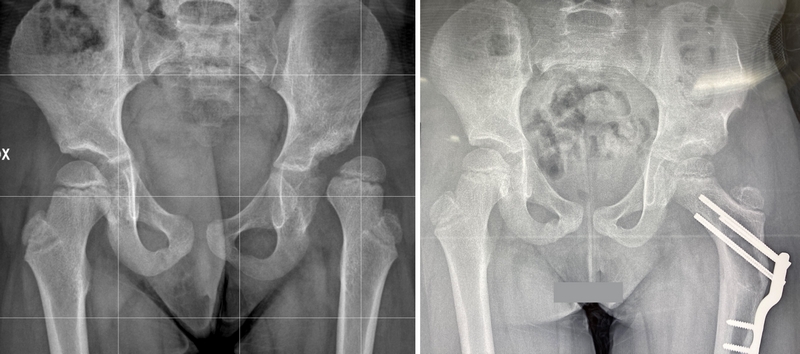

Ad esempio, le osteotomie di riorientamento del bacino (osteotomia di Salter per esempio) vengono utilizzate quando è necessario cambiare l’orientamento dell’acetabolo. In questi casi, viene eseguita l’osteotomia al di sopra dell’acetabolo, l’osso del bacino viene ruotato nella giusta direzione e fissato con dei fili di metallo (Kirschner) fino alla guarigione.

Lo sviluppo osseo dei pazienti affetti da displasia o lussazione congenita dell’anca deve essere seguito nel tempo. Se lo sviluppo non è regolare, si evidenziano deformità a carico del tetto (tetto sfuggente) ed eventualmente anche a carico del femore (valgismo del femore, ecc).

In questi casi è possibile associare alla tettoplastica anche un intervento correttivo sul femore.

Viene eseguita un’osteotomia (=sezione dell’osso) del femore, l’osso viene piegato nella direzione corretta e fissato in modo che possa guarire nella giusta posizione.

Un tempo utilizzavamo i puntali e i fili di Kirschner percutanei, cioè lasciati sporgere al di fuori della cute, al di sotto del gesso. Questo sistema però richiedeva lunghi tempi di immobilizzazione in gesso e lasciava cicatrici antiestetiche (infossate, ecc); in qualche caso poi i puntali non garantivano adeguata stabilità e si perdeva la correzione.

Per tale motivo questo sistema è stato ormai superato dall’utilizzo di placche metalliche più moderne che garantiscono più stabilità e riducono i tempi di immobilizzazione in gesso di questi bambini.